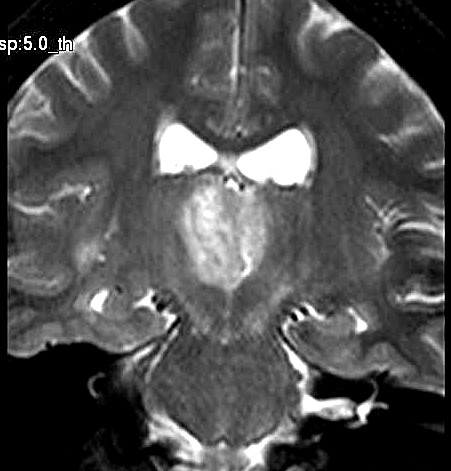

| Fem. 17a. |

| Nódulo sólido homogêneo preenchendo o III ventrículo, com limites precisos, com hipossinal em T1 e hipersinal em T2 e FLAIR, que se impregna por contraste paramagnético. Lesão menor implantada no assoalho do IV ventrículo provavelmente representa disseminação por via liquórica. |

| AXIAIS, FLAIR | T2 | |

| F. 17a. Tumor teratóide rabdóide atípico de III ventrículo. RM | HE | VIM, GFAP | HHF35, desmina, 1A4 | AE1AE3, EMA |